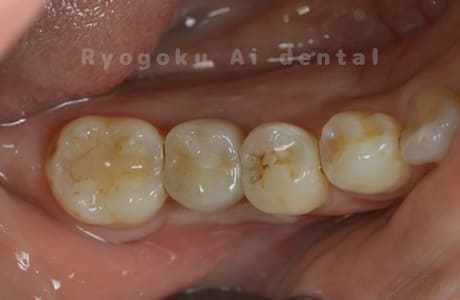

Case07

- 原因

- 右下6番歯根破折

-

- 治療内容

- インプラント治療

- 治療費用

- 約600,000円

右下の腫れが治らないとの事でご来院された患者様です。歯が割れていたため、抜歯を行い、骨に代わるお薬を入れ、インプラントを埋入致しました。経過良好で大変満足していただけました。

<リスク・副作用>

治療後、痛みや違和感、出血、腫れなどが出る事があります。喫煙者、糖尿病などの方の場合、歯が生着しない場合があります。